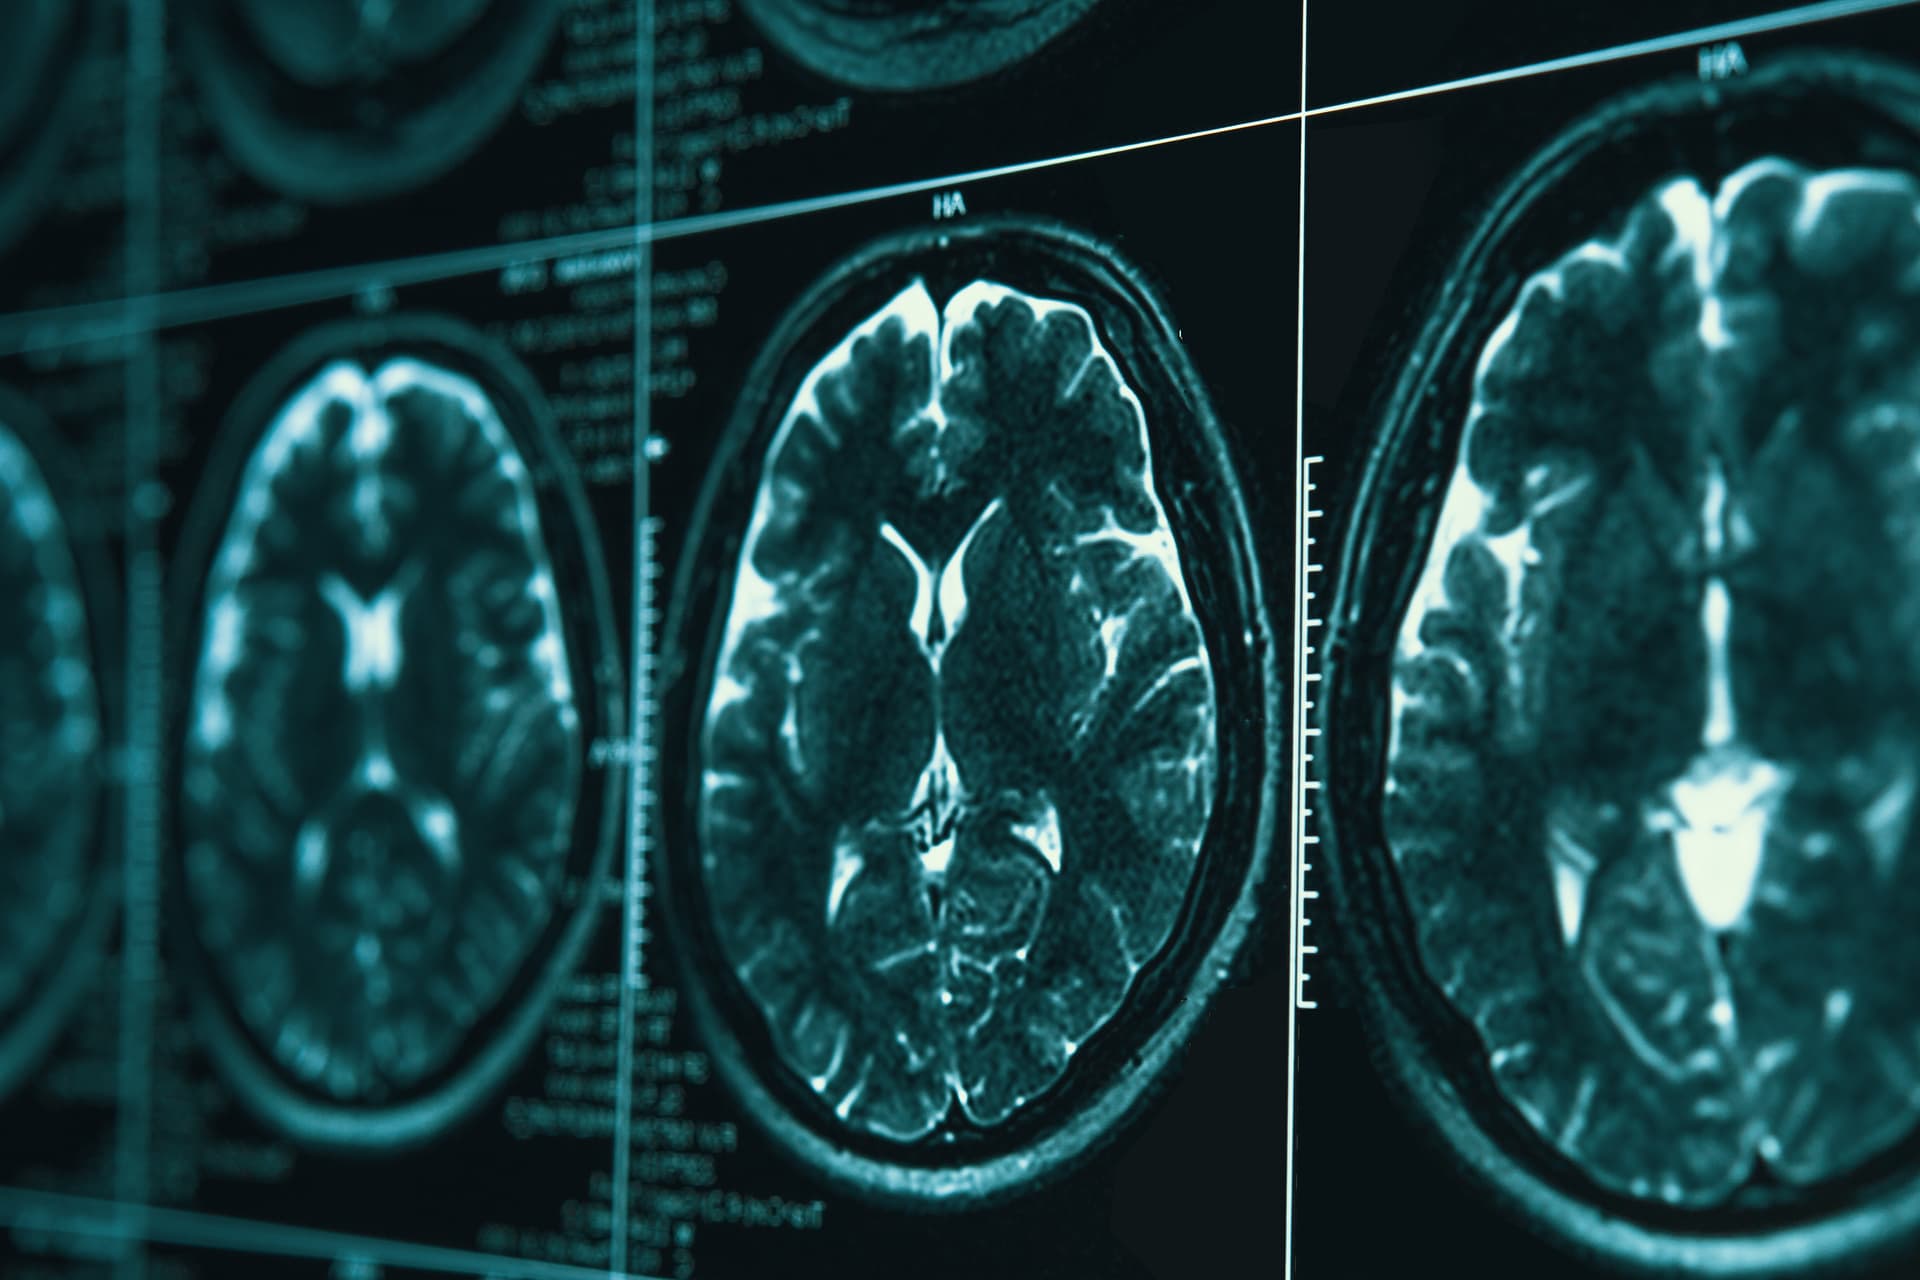

Making real gains in war on Alzheimer’s

Alzheimer's disease, marked by amyloid plaques and tau tangles, affects millions, with new research exploring genetic, lifestyle, and immunological factors for potential treatments and prevention.